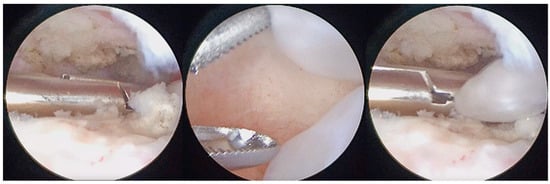

The arthroscopic treatment of TMJ chondromatosis encompasses various procedures depending on the extent of the disease and the individual patient’s needs. These include removal of LB and treatment of synovia (scarification, removing of hyperplastic synovia). All patients were treated under general anaesthesia with nasal intubation. The same surgeon performed all surgeries (S.S.). The Henke-Sass Wolf (Tuttlingen, DE) arthroscopic system (1.9 mm, 0°) was used. TMJ was identified by palpation by opening and closing the patient’s mouth. A 19 G needle was introduced in the upper compartment and saline was injected enlarging the upper joint space through a pumping technique. A small incision on the injection point was performed with a No. 11 scalpel blade. At this point, the needle was removed and the trocar with the arthroscopic sheath was inserted into the posterior recess of the upper joint space. The trocar was then removed, and the arthroscope was inserted into the arthroscopic sheath, providing a clear view of the TMJ upper compartment and of the signs of SC such as osseus contours, hyperplasia of the synovia, subsynovial nodules, nodules, LBs, synovial polyp, synovitis, chondromalacia, perforation of the disk, and adhesions (Figure 1, Figure 2 and Figure 3). This first port acted also as irrigation port, and saline was used to continuously wash out the joint space, removing any debris or remaining LBs. Using a triangulation technique, a second cannula of 2.0 mm was introduced in the anterior recess of the superior joint space, and it was used for instrument passage, drainage, and LBs evacuation (Figure 4). However, changing to a larger cannula system, like a 3.0 mm system, which may provide adequate clearance for removal of large LB, was also performed. Forceps were used to remove the LBs larger than the cannula diameter (Figure 5). LBs were also fragmentated using a cold ablation (coblation) radiofrequency device (COBLATORTM II Surgery System, Smith & Nephew, UK) (Figure 6 and Figure 7). Coblation is a process that uses a radiofrequency electrical energy passing through saline solution, producing plasma that can be applied precisely to tissues to break molecular bonds within cells. This device was also used to remove the hyperplastic synovia and perform a selective synovectomy of the metaplasic areas. The nodules attached to the subsynovial connective tissue were also precisely coblated. Moreover, coblation provides the possibility to split large LBs (>3 mm) in order to ease their washout or removal. Specimens from the affected synovia and LBs were harvested and sent to the Pathology Department to provide a definitive diagnosis (Figure 8). Manual manipulation of the mandible was performed during the approaches and through the whole surgery to reach all joint zones. At the end of the procedure, an intrarticular injection of 1 cc of hyaluronic acid was performed to ease articular mobilization and for anti-inflammatory purpose, then the arthroscopic sheath and the cannula were removed. Therefore, incisions were closed with sutures.

Figure 5.

Arthroscopic removal of LBs and synovial nodules using forceps.

Figure 6.

Coblation of metaplasic nodules and division of large LBs to ease their washout.